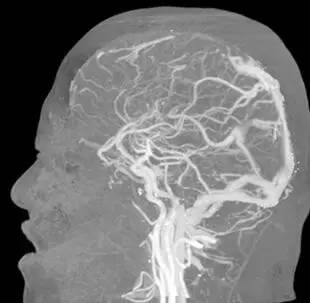

诊治经过:考虑存脑疝,予开颅血肿清除+去骨瓣减压术,,术后予降颅压对症治疗。考虑患者可能存颅内静脉窦血栓,行MRV及全颈脑血管造影术,示“左侧横窦闭塞 矢状窦、右侧横窦血栓形成”。予华法林抗凝治疗。出院PT-INR:2.11。门诊随访中。

▼影像资料